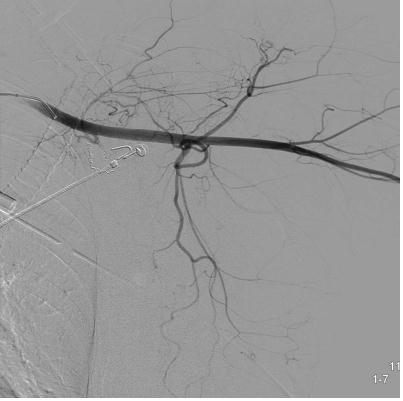

胰十二指肠上、下动脉瘤(sandwich 技术+瘤囊填塞技术)

肠系膜上动脉造影显示胰十二指肠上动脉后弓及前弓各有动脉瘤 |

选择性第一空肠动脉造影显示胰十二指肠下动脉起自第一空肠动脉,其起始部见假性动脉瘤 |

微导管经瘤腔释放微弹簧圈阻塞动脉瘤远端胰十二指肠下动脉前弓,避免侧支动脉充盈动脉瘤 |

阻断动脉瘤远端后同时进行动脉瘤内填塞 |

肠系膜上动脉胰十二指肠下动脉另一分支造影显示其起始部动脉瘤 |

动脉瘤囊内微弹簧栓子填塞 |

填塞后 |

术后动脉造影 |